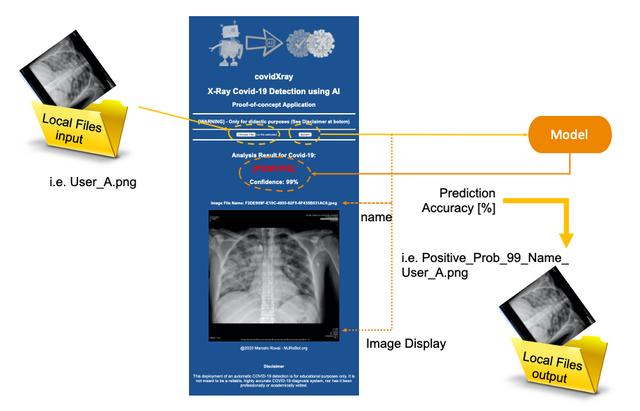

下图为我们提供了最终应用程序如何工作的基本概念:

X光扫描胸部图像(User_A.png),应用程序将图像存储在web应用程序的计算机上,决定图像是否属于受病毒污染的人(模型预测:[阳性]或[阴性])。在这两种情况下,应用程序都会输出预测的准确性(模型准确度:X%)。

为了避免两者都出错,将向用户显示原始文件的名称及其图像。图像的新副本存储在本地,其名称添加一个预测标签,并且加上准确度。